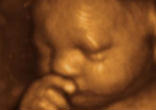

When I Was in the Womb: We Must Not Retreat in Building a Culture of Life Watch

Jesus Christ lived in the first home of the whole human race. He progressed through every stage of every child's beautiful growth. He is as ... continue reading

Am I Not Your Neighbor? New Symbol and National Campaign to Defend Our First Neighbor in the Womb Watch

These children are our first neighbors in the first home of the whole human race, their mothers' womb. It is always wrong to kill our ... continue reading